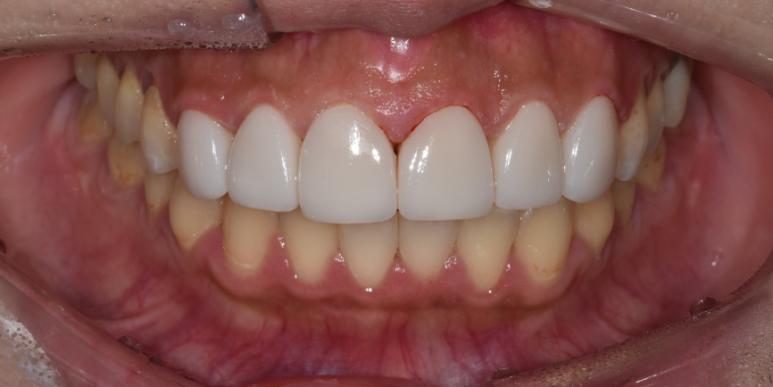

환자분은 20대 초반의 어린 나이임에도 치아 변색이 심해 스트레스가 많았던 분입니다.

그래도 교정을 마친 상태라 치아배열은 좋은 편이셨기에, 최소량만 치아를 다듬고 라미네이트 시술을 진행할 수 있었는데요.

기존 치아와 자연스러운 색상을 제안해 드렸지만, 환자분이 더 밝고 환한 치아를 원해하셔 니즈에 맞게 진행하였습니다.

(전) 2022-05-11, (후) 2022-05-18

보철물 색상이 다른 치아보다 밝기는 하지만,

웃거나 말할 때는 윗니만 보이셔서 실제는 위 사진보다 훨씬 더 자연스러운 느낌이 있었습니다.

어렸을 때부터 누런 치아가 항상 콤플렉스였는데 단기간 내 하얗고 밝은 치아를 얻게 돼서 너무 기쁘다고 좋아하시는 모습을 보며, 저희 의료진도 흐뭇했던 사례인데요. ^^

이후 치아미백을 진행하신다면, 전체적으로 밝은 치아를 유지하는 데 도움이 될 수 있다고 안내해드리고, 치료를 마쳤습니다.